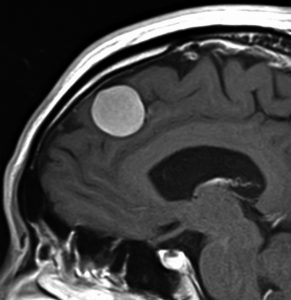

典型的な髄膜腫

この髄膜腫は中程度の大きさのものです。円蓋部髄膜種という最も多い最も手術の簡単なタイプです。麻痺や失語症やてんかんなどの症状はありません。とても美しくて若い女性の髄膜腫でしたが,子供に遺伝はしませんし,癌などと違ってタバコなどこれといった原因がなくて発生するものです。

MRIでの髄膜腫の見え方は撮影の仕方によっていろいろです。左からT1強調画像,T2強調画像,フレア画像といいます。腫瘍の横に小さく白い領域がありますが,これは脳の腫れた部分で脳浮腫といいます。髄膜腫があると周囲に脳浮腫が生じることがあります。

最も見やすいのが,ガドリニウム造影剤を注射して撮影するものです。一般的に髄膜腫は造影剤で白く映し出されます。この腫瘍は左脳側にあります。MRIの軸面という輪切りの写真では左右が逆になりますから注意してください。脳を下から見た図になっています。MRIはいろいろな方向から腫瘍を見ることができますが,右は冠状断という正面から見た図です。よく見ると腫瘍の上と下のはじっこに線状に糸を引いたように造影される部分があります。これをテールサイン(しっぽのサイン)といいます。腫瘍が硬膜に沿って延びている可能性があることを示しています。